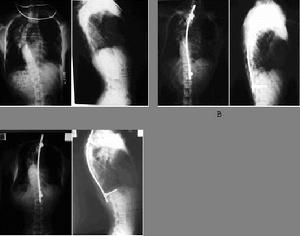

脊柱侧凸脊柱的某一段偏离中线,形成曲线,称脊柱侧凸。侧凸畸形可与超过生理性的前凸或后凸畸形同时存在。侧凸的椎体伴有旋转畸形,侧凸程度愈大,旋转愈严重。使肋骨和胸廓变形,两侧不对称,严重影响心肺功能。

本病以女性为多,在儿童期身体增长慢,畸形并不明显,即使轻微畸形,亦无结构变化,容易矫。正但此时期不易被发现,患者至10岁以后,椎体第二骨骺开始加速发育,侧凸畸形的发展,即由缓慢转为迅速,1-2年内可以产生较明显的外观畸形,多数侧凸发生在胸椎上部凸向右侧,其次好发于胸腰段凸向左侧着较多,脊柱侧凸所造成的继发性胸廓畸形,如畸形严重,可引起胸腔和腹腔容量减缩,导致内脏功能障碍。如心脏有不同程度的移位,心搏加速,肺活量减少,消化不良,食欲不振,神经根在凸侧可以发生牵拉性症状,凹侧可以发生压迫性症状,神经根的刺激,可以引起胸和腹部的放射性疼痛,亦有引起脊髓功能障碍者,由于内脏功能障碍息者全身往往发育不佳,躯干矮小,体力较弱,心肺储备力差.。 医学百科网 | YxBaike.Com